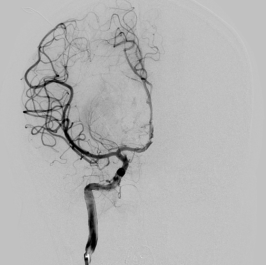

▲术后复查头部CT显示颅内血肿清除且无再次出血现象。